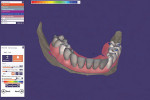

The optical scan files were imported into a dental laboratory planning software (exocad, exocad GmbH) and the scan of the prosthesis and edentulous ridge with fixed housings was aligned using an alignment algorithm within the software. Virtual prosthetic teeth were arranged according to the positions within the aligned implant overdenture and a fixed prosthesis base was designed (Figure 8). The prosthesis was designed in a way where the teeth arch can be manufactured separately from the base. The prosthetic base was 3D printed using a pink biocompatible resin (Denture 3D+, NextDent) on a laboratory-grade 3D printer (NextDent 5100, 3D Systems) (Figure 9). Additionally, the prosthetic tooth arch was 3D printed on the same printer using a tooth shade biocompatible resin (C&B MFH, NextDent). The teeth were joined to the denture base using pink biocompatible resin and the prosthesis was stained and glazed using a light-curing resin (OptiGlaze, GC America Inc.). The maxillary prosthesis was relined using a reline jig (Lang Dental) and autopolymerizing acrylic resin (Diamond D, Keystone Industries).

The optical scans made on the initial patient visit were imported into a dental laboratory software (Dental System, 3Shape) for designing the framework and definitive prosthesis. The optical scan of the edentulous ridge with the housings was virtually blocked-out and retentive mesh was placed (Figure 11). The framework outline was designed using the software and supporting bars were placed between the initial design (Figure 12). The completed mandibular framework was designed around the shape of the interim prosthesis that had been previously designed to ensure sufficient strength and esthetics (Figure 13). The initial framework design was virtually copied and a new design file was created. Virtual denture teeth were positioned according to the original interim prosthesis design and a denture base was designed to match the previously designed framework (Figure 14). Using a laboratory milling machine (K5, VHF), the mandibular framework was milled in a fiber-reinforced polymer material (Trinia, Bicon Dental) (Figure 15). The prosthetic teeth and base were milled on the same machine in a high-strength PMMA denture material (Ivotion, Ivoclar Vivadent) (Figure 16 and Figure 17).